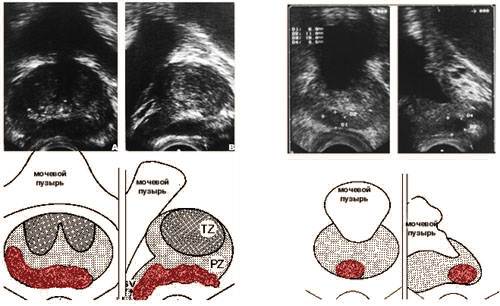

Трансректальная ультразвуковая томография.

Опухоль предстательной железы.